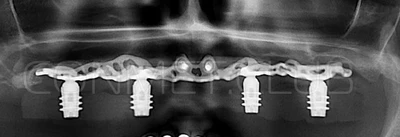

И в-четвертых: небольшой фрагмент из операции по восстановлению всех утраченных зубов на верхней челюсти. По сути эта операция полностью повторяет протокол и этапность операции представленной в первой части статьи, за исключением того, что искусственные зубы были зафиксированы сразу после операции. Со слов самой пациентки, процесс жевания был совершенно безболезненным с самого первого дня.

Клинические работы с субпериостальными имплантатами производства Конмет, проведенные в 2019 году, позволили унифицировать интерфейс данных имплантатов под современный цифровой протокол. Более того, необходимые конструкционные элементы были введены в официальную базу под программу Exocad. Что позволило сократить время изготовления зубного протеза до 1-3 дней!